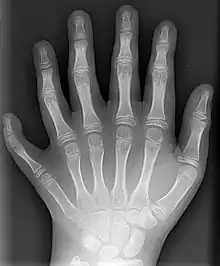

X-ray of the left hand of a ten-year-old boy with polydactyly

A number of genetic disorders affect the hand. Polydactyly is the presence of more than the usual number of fingers. One of the disorders that can cause this is Catel-Manzke syndrome. The fingers may be fused in a disorder known as syndactyly. Or there may be an absence of one or more central fingers—a condition known as ectrodactyly. Additionally, some people are born without one or both hands (amelia). Hereditary multiple exostoses of the forearm—also known as hereditary multiple osteochondromas—is another cause of hand and forearm deformity in children and adults.[20]